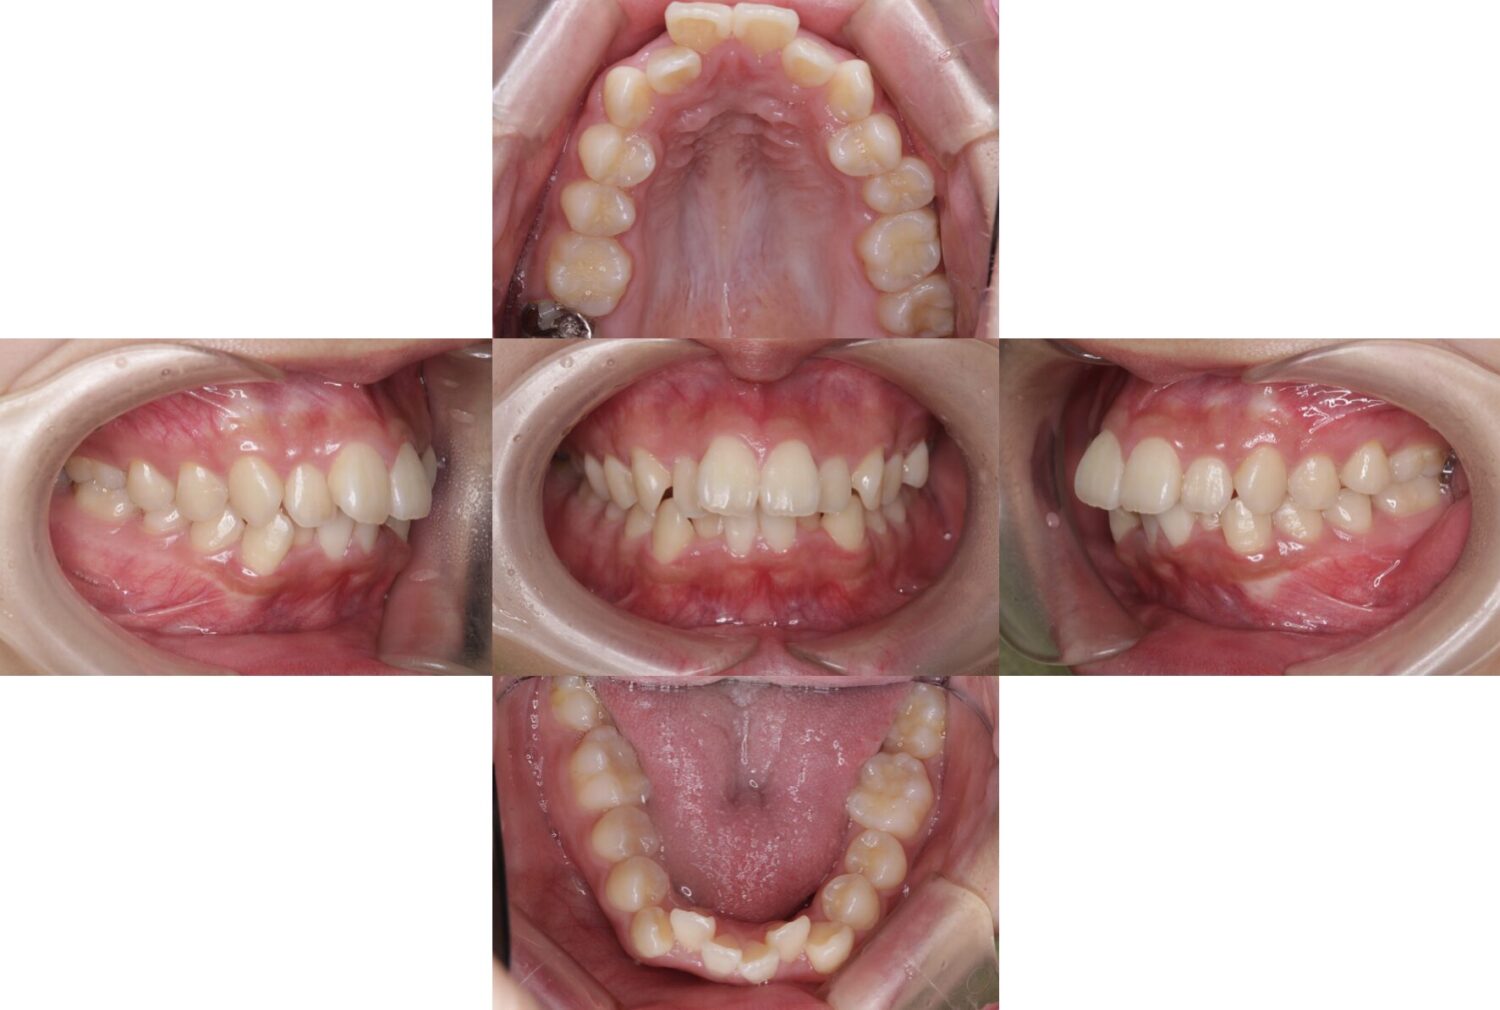

治療前の状態|前歯の突出感と全体的なガタつきがありました

治療前は、前歯が上下とも前方に突出しており、口元の閉じづらさにつながっていました。

また、2番目の歯が内側に引っ込み、3番目の歯が外側に飛び出している状態で、歯列に強いガタつきが見られました。

このような歯並びでは、見た目だけでなく、歯ブラシが届きにくい部分が増え、虫歯や歯肉炎のリスクが高くなることがあります。

そのため、見た目の改善だけでなく、清掃性や噛み合わせの改善も考えて治療を進めました。